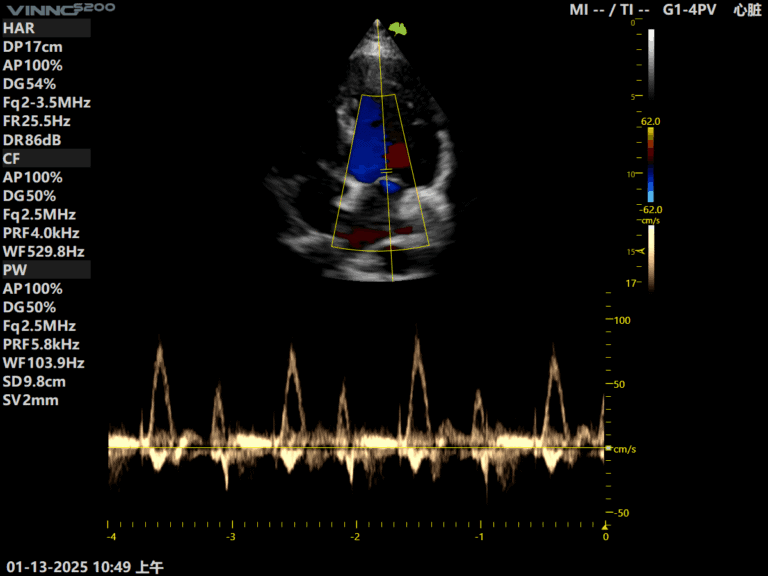

Ecograful VINNO S200 este versatil si performant, recomandat clinicilor care au nevoie de un echipament fiabil pentru diverse specialitati: interne, gastroenterologie, ginecologie, ecografie generala etc.

- Functii avansate precum module cu AI, elastografie si Doppler color de inalta rezolutie

Citeste mai multEcograf VINNO S200 – solutie moderna pentru evaluari zilnice

Ecograf VINNO S200 – solutie moderna pentru evaluari zilnice Echipa Numeris Medical a finalizat cu succes instalarea ecografului VINNO S200 in cabinetul domnului dr. Ipate Florin, medic specialist cardiologie din Calarasi.In cardiologie, claritatea imaginii, stabilitatea semnalului si sensibilitatea Doppler sunt…